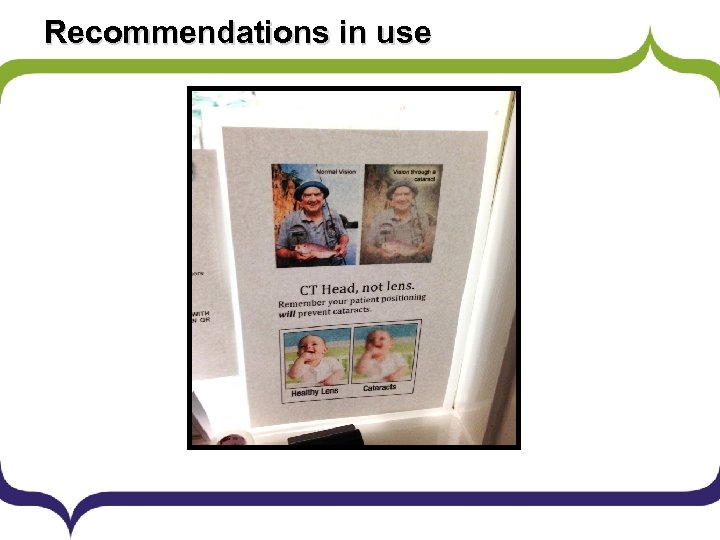

Recommendations in use

Delivery Plan 1. A replacement head sponge to be ordered as a matter of urgency. a) In the interim, the use of a rolled up towel/gown was suggested. 2. The importance of correct positioning in view of the recent ICRP press release and IRMER legislation was reinforced with an email to the CT radiographers and reminder posters within the CT control rooms. 3. Re-audit in 3 months.